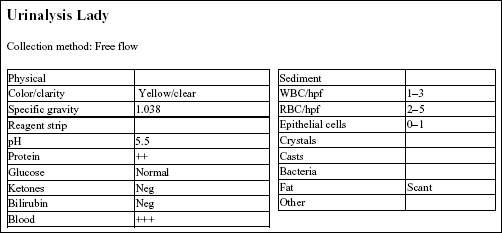

Lady, a 15-year-old F(s) Chihuahua X dog, had lethargy and a severe heart murmur.

The urine SG indicates adequate renal function. Protein at 2+ could be significant; however, this could be better assessed by urine protein to creatinine ratio. Blood reaction appears to be due to mild hematuria. This is a free flow sample, so hematuria is unlikely to be iatrogenic (as seen with cystocentesis sampling), unless the bladder had been manually compressed to obtain the sample.